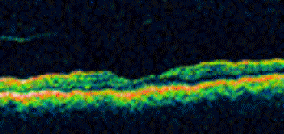

Learn more about treating a macular hole from authoritative sources.